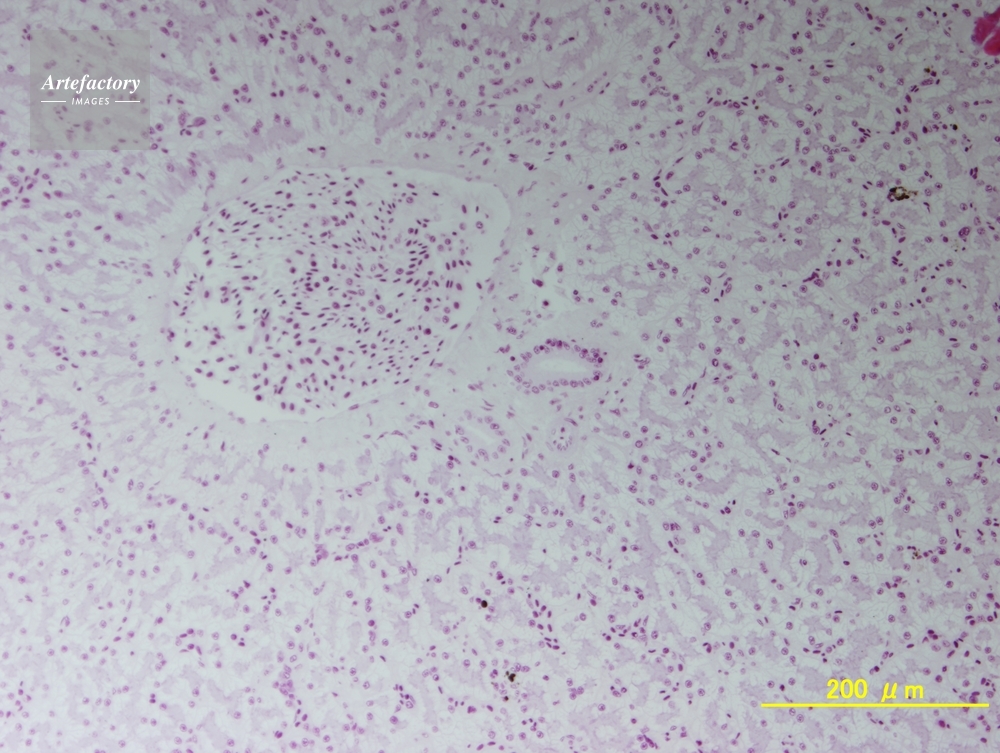

| 作品タイトル | カエル,肝臓 | モデルリリース | なし | |

| 作家 | OLYMPUS CORPORATION Technolab | プロパティリリース | なし | |